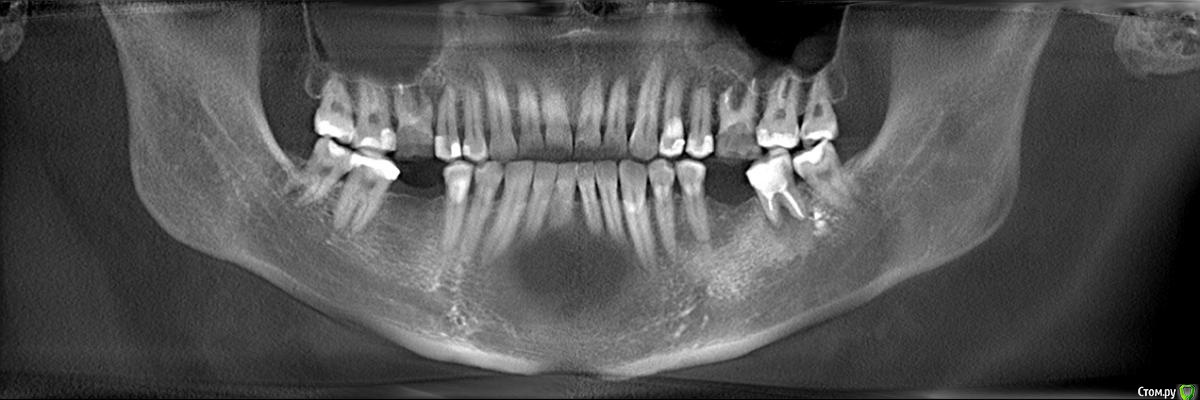

Faramir Опубликовано 18 апреля, 2019 Поделиться Опубликовано 18 апреля, 2019 (изменено) Здравствуйте.Подскажите пожалуйста, возможно ли лечение верхних шестерок и нижней семерки для устранения очагов воспаления?Правая шестерка в течении месяца два раза болела с образованием болезненного валика на десне над ним но после полосканий проходила. Над левой шестеркой больше полугода свищ над которым изредка надувается и лопается белый шарик. Зубы лечились около 15 лет назад. До этого года не беспокоили. Шестерки с помощью установки в каналы/канал стекловолоконных штифтов и приклеивания на них отдельно изготовленной накладки/коронки. Семерка лечилась путем обычного заполнения каналов и последующего пломбирования. Изменено 18 апреля, 2019 пользователем Faramir Ссылка на комментарий

krokomot Опубликовано 18 апреля, 2019 Поделиться Опубликовано 18 апреля, 2019 Удалять! шестёрки, седьмой снизу нужно еще покрутить кт и сделать прицельный снимок. 2 Ссылка на комментарий

krokomot Опубликовано 18 апреля, 2019 Поделиться Опубликовано 18 апреля, 2019 Я не разбираюсь. Просто хотелось бы аргументированных ответов и прогнозов.Прочитайте правила форума, мы не проводим обучение пациентов, и что бы вы начали разбираться вам нужно много изучить, оценив вашу ситуацию, я вам ответил на ваш вопрос, верхние шестерки не подлежат лечению не потому что их каналы можно перелечить, а потому, что слишком мало тканей осталось у зубов, зубы разрушены слишком значительно и лечение каналов проводится в подходящих для дальнейшего протезирования зубах, моё мнение удалять. 2 Ссылка на комментарий

suballex Опубликовано 19 апреля, 2019 Поделиться Опубликовано 19 апреля, 2019 Обучать конечно не надо, но привести пару веских аргументов считаю каждый доктор имеет возможность. Пациенту от этого легче принять решение. Иначе образуется информационный вакуум в котором можно пойти по ложному пути. В любом случае спасибо за ваш ответ.После проведения всех манипуляций, от зубов ничего не останется. Прогноз их восстановления не благоприятный. Это раз.Вероятность успеха повторного эндодонтического лечения не более 50%, для зубов, которые гораздо менее сложные, чем ваши. Это два.Аргументов достаточно? 1 Ссылка на комментарий

dentikl Опубликовано 19 апреля, 2019 Поделиться Опубликовано 19 апреля, 2019 каждый доктор имеет возможность. Пациенту от этого легче принять решение. ситуация для очной консультации.по снимкам-шансов 0 Ссылка на комментарий

red_butler Опубликовано 23 апреля, 2019 Поделиться Опубликовано 23 апреля, 2019 Объём оставшихся твёрдых тканей не позволяет прогнозируемо восстановить зубы+1 удалять Ссылка на комментарий